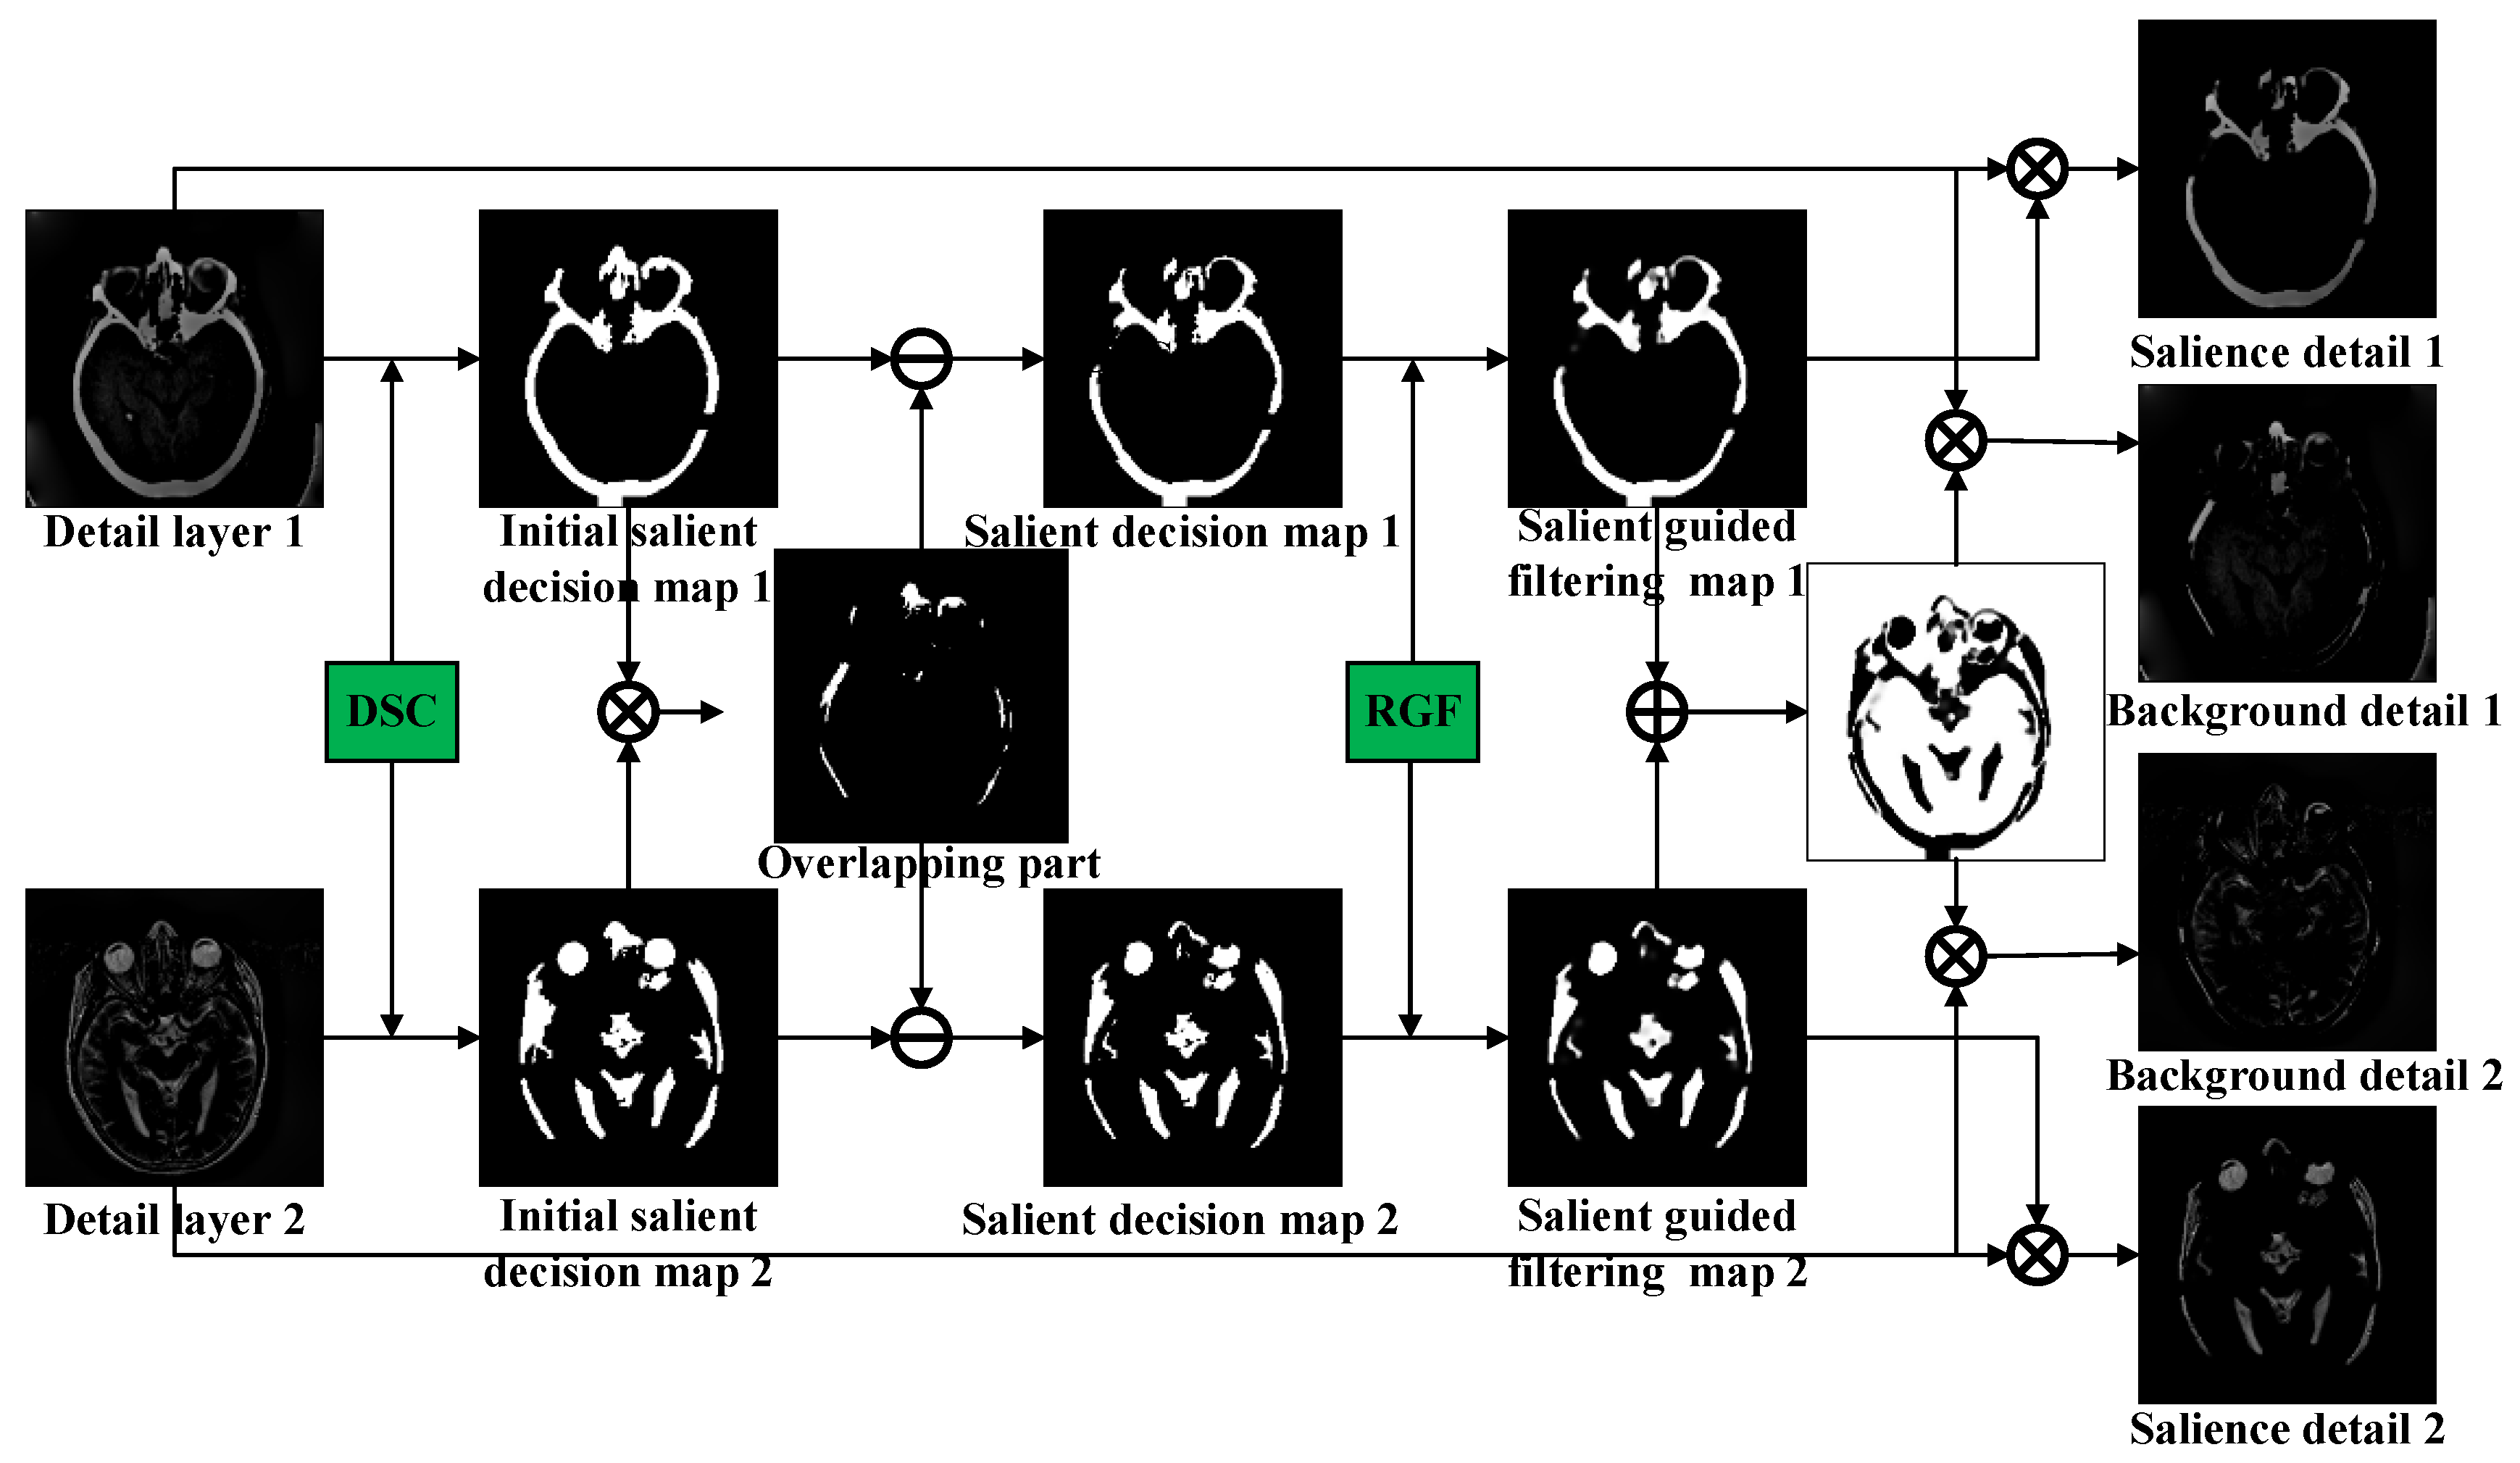

3.2. Decomposition of Detail Layer Based on DSC-RGF Algorithm

- A detail-layer fusion rule based on DSC and RGF is proposed, which fully considers the low contrast between the target and background.